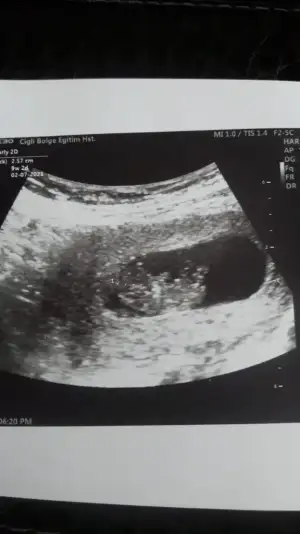

• IMG_20200720_233352.webp

IMG_20200720_233352.webp

5,8 KB · Görüntüleme: 51

Bu haftaya kadar erkek dedin canım nubda kız diyorsan kızdır ozaman nasip doktorda emin değilim ama kıza benziyor dedi 3. Kızımız gelecek bu durumda🙈

Önceki usg kaç haftalıktı kese arada tutmuyor cnm hayırlısı olsun sizin için😊

Tahmin etsem dogru olmaz tahminin yanlış dersiniz 😉 12-13 hafta olursa paylaşın şimdilik kız ama şimdilik emin olamadım 😉